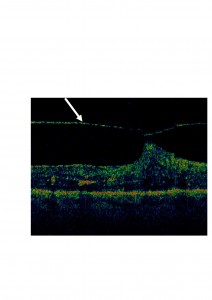

Os mostramos unas imágenes de un paciente atendido en nuestro Hospital.

En la primera podéis observar en la OCT un punto de anclaje del vítreo (señalado con flecha) sobre la retina.